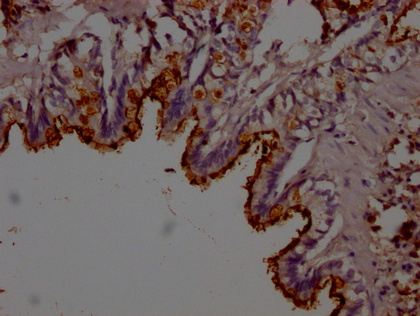

IHC image of CSB-PA012816LA01RA diluted at 1:200 and staining in paraffin-embedded rat lung tissue performed on a Leica BondTM system. After dewaxing and hydration, antigen retrieval was mediated by high pressure in a citrate buffer (pH 6.0). Section was blocked with 10% normal goat serum 30min at RT. Then primary antibody (1% BSA) was incubated at 4°C overnight. The primary is detected by a Goat anti-rabbit polymer IgG labeled by HRP and visualized using 0.05% DAB.